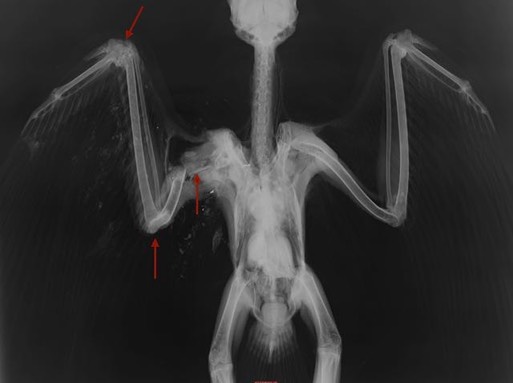

Red-tailed Hawk 18-018

An adult Red-tailed Hawk was found near Echo, OR. A radiograph showed that he had been shot. The wound was two or three weeks old, explaining why the hawk was so thin. The damage was too extensive to repair and he was humanely euthanized.